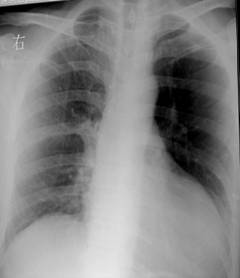

照片名称:风心病,梨型心